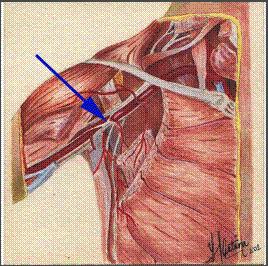

Síndrome de Hiperabducción.

• A este nivel, los tres elementos del paquete vasculonervioso pasan por detrás del tendón del músculo pectoral menor en su inserción con el proceso coracoideo de la escápula. fig # 1 y 4 El diagnóstico se realiza con la maniobra de hiperabducción del brazo. (foto#7) La sintomatología es similar al del Síndrome Costoclavicular, pero suelen ser menos acentuados los síntomas y signos venosos.